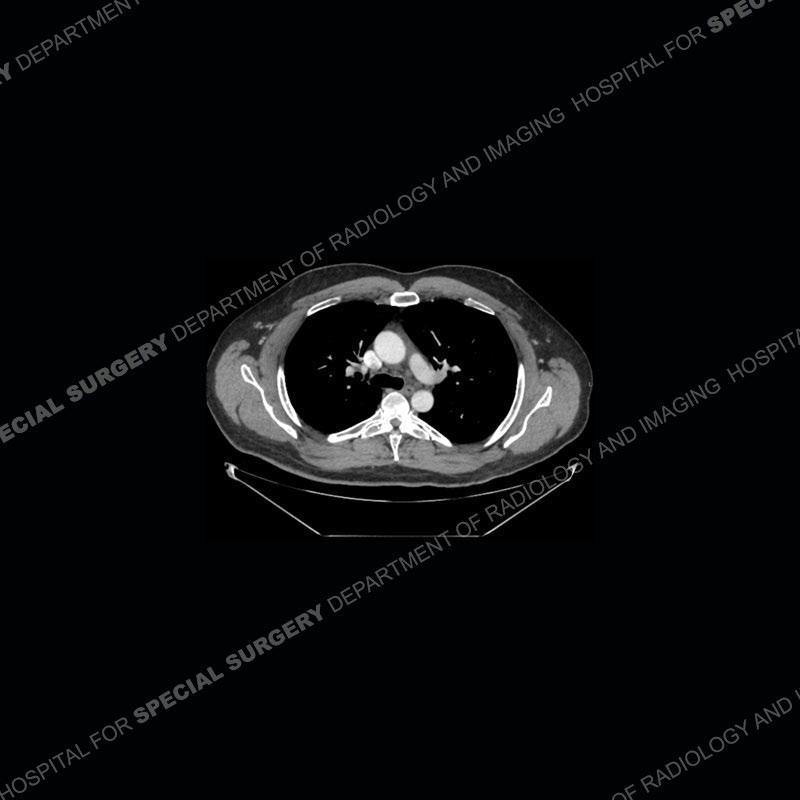

The chest radiographs demonstrate a leftward deviation of the trachea. CT images demonstrate a large, somewhat heterogeneous mass of the thyroid that extends outside the confines of the thyroid tissue. There is a subtle, enhancing soft tissue mass of the proximal right humerus. Slightly prominent mediastinal lymph nodes are present with additionally, multiple supraclavicular lymph nodes.

Over the years we have shown a couple of these cases which may be considered more so an “eye test” then anything else. In clinical practice, these are often very difficult cases as the initial finding of the tracheal deviation may be easily overlooked. Screening radiographs are clearly most often used to assess cardiopulmonary function before induction of anesthesia but at times other findings of great and unfortunately grave consequence can be found. The evaluation of the incidental thyroid mass on CT and MRI is an ever changing situation. Parameters such as age of patient, extension outside of the thyroid, enhancing nodules, and local invasion of lymph nodes are evaluated to see if a lesion needs to be further evaluated.